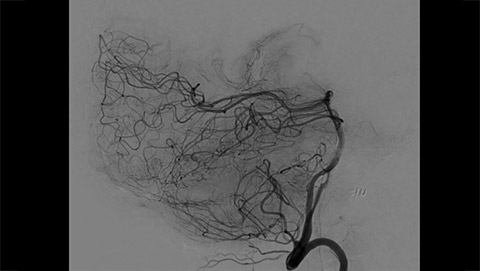

Whether visualizing the smallest vessels in an aneurysm, precisely placing a flow diverter, seeing beyond the clot, or working slowly through a complex AVM, the challenge is to see clearly and navigate effectively. You must quickly assess the problem and confidently target the lesion, while preserving healthy tissue. Our AlluraClarity family of X-ray systems with ClarityIQ technology enables you to smoothly maneuver through complex anatomy at 73% reduction in dose. Multimodality Live Image Guidance and procedure-based applications help improve workflow. Sign up to receive exclusive updates on Live Image Guidance.

MR/CT Roadmap visualizes lesion boundaries and corresponding vascularization, while helping you to manage X-ray dose and contrast medium. 3D Roadmap provides full 3D view for dynamic guidance of guidewire and catheter navigation through complex vascular lesions.

2D navigation with Roadmap Pro is supported by automatic, real-time motion compensation and decreased subtraction artifacts. Clinical modes are optimized for various clinical applications.